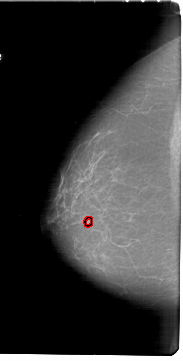

A_1800_1.LEFT_MLO

LEFT_MLO LINES 6691 PIXELS_PER_LINE 3361 BITS_PER_PIXEL 12 RESOLUTION 43.5 OVERLAY

FILE: A_1800_1.LEFT_MLO.OVERLAY

TOTAL_ABNORMALITIES 1

ABNORMALITY 1

LESION_TYPE MASS SHAPE LOBULATED MARGINS ILL_DEFINED

ASSESSMENT 4

SUBTLETY 3

PATHOLOGY BENIGN

TOTAL_OUTLINES 1

BOUNDARY